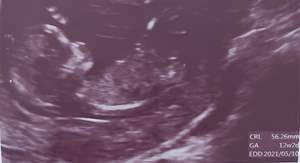

متخصصین تشخیص جنسیت از روی سونوگرافی ان تی لطفا بیایین